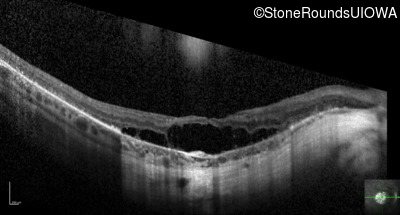

Optical Coherence Tomography - Right - 20/125

Exemplar / OCT Stack

OCT Stack